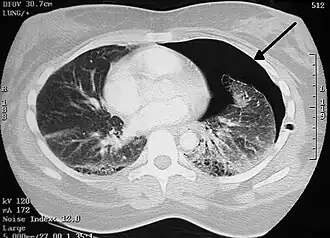

CT-scan bij een pneumothorax. De linkerlong (rechts in beeld) is geschrompeld en gedeeltelijk omgeven door lucht. Tussen de ribben is waarschijnlijk de doorsnee van een drain zichtbaar